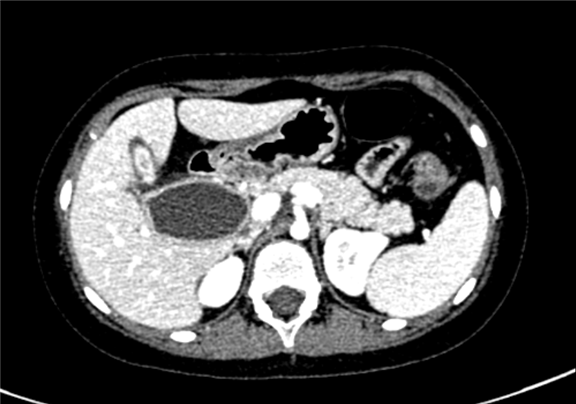

上腹部增强CT:先天性胆管囊状扩张(IV型)可能性大,胆总管十二指肠胰腺段及十二指肠壁内段显示不清, 胆囊壁增厚,肠系膜根部散在散在略大淋巴结

术前CT检查:

动脉期

静脉期